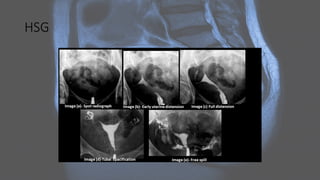

HSG

Radiographic features

Radiographic features Ultrasound: • shouldbe performed initially • confirms any structural abnormalities of the genital tract • sometimes cannot help to identify the type of MDA (especially on 2D imaging alone) • 3D coronal transvaginal imaging has a high degree of diagnostic accuracy and ideally should be performed in the secretory phase of the menstrual cycle

MRI: • valuable non-invasivetechnique • evaluation of the female pelvic anatomy • accurate Müllerian duct anomaly classification